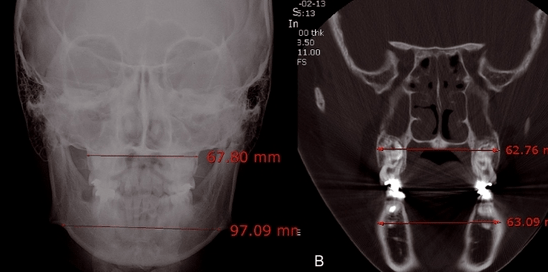

Die Abbildung 4a zeigt eine PA-Aufnahme einer 16-jährigen Patientin mit einer maxillo-mandibulären Breitendifferenz von ca. 30mm. Hier wird eine knöcherne Expansion mit­tels operativer Methode gefordert, da der durchschnitt­liche Wert für Breitendifferenzen nach Betts et al. für Erwachse­ne lediglich bei 19,6mm liegt. Jedoch zeigt die Differenz der bukkalen basal­knöcher­nen Breite in der fron­talen CT-Aufnahme glei­cher Patientin (Abb. 4b) im molaren apikalen Bereich einen Wert unter 1mm sowie eine sehr gute posteriore Okklusion. In solchen Fällen ist es schwierig, eine skelettale transversale Diskrepanz zwischen Ober- und Unterkiefer zu diagnostizieren. Denn die­se Differenzen könnten auch auf den skelettalen Charakter koreanischer Patienten zurückzuführen sein. Jedoch steht fest, dass die Referenzpunkte wie JL-JR oder AG-GA den Zahnbogencharakter nicht immer vollständig widerspiegeln. Ei­ne genaue Beurteilung der Zahnachse erfolgt durch die Analyse der Okklusion der individuellen Patientenmodelle im Artikulator und ist somit besser als eine alleinige radiologische Messmethode.